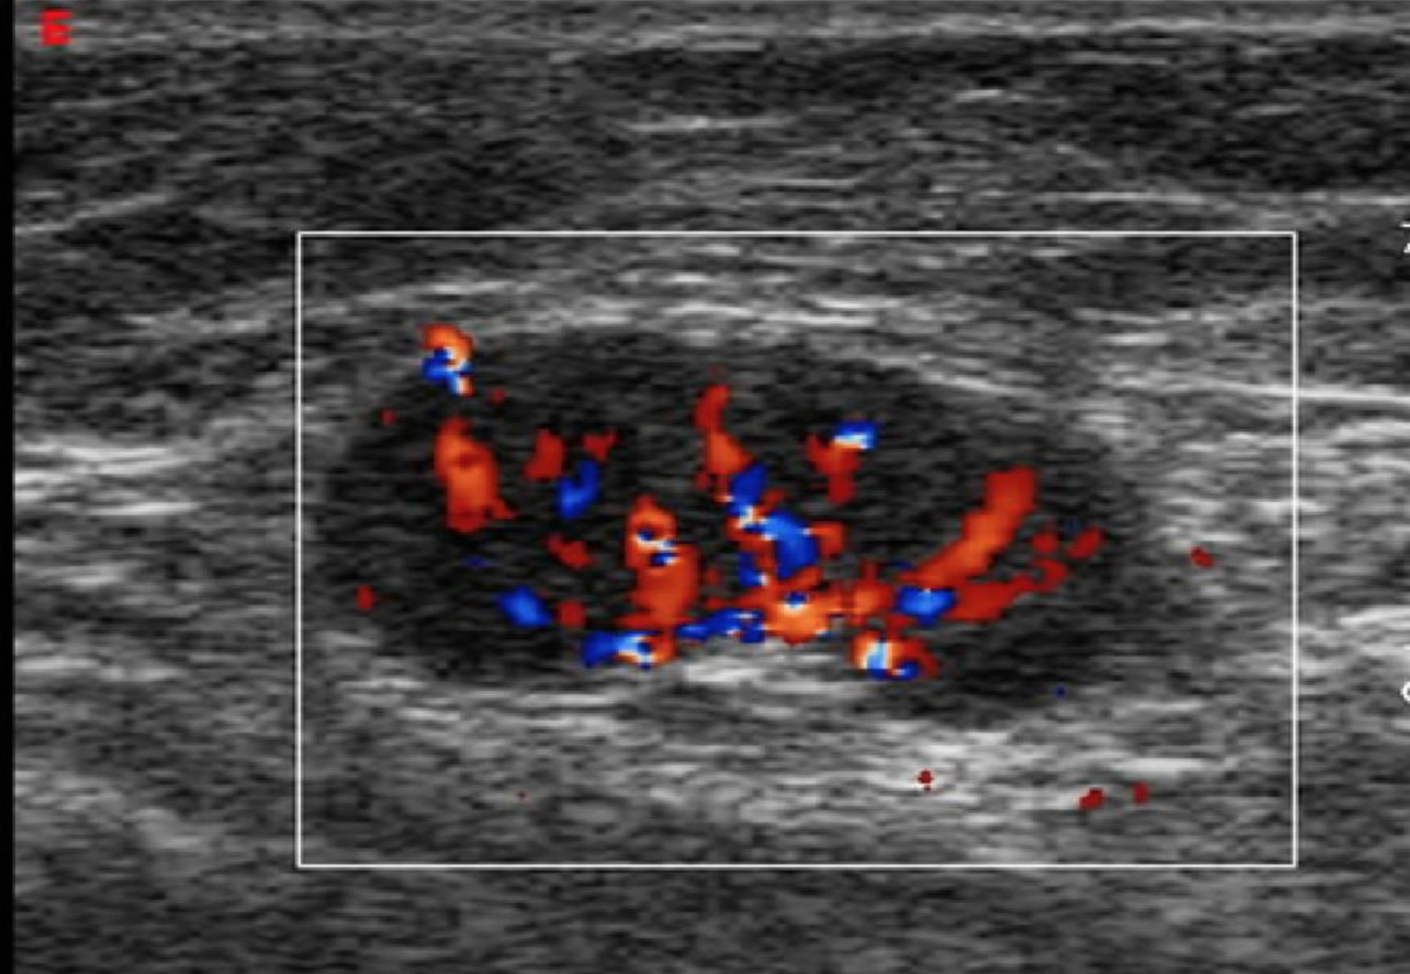

- Lymph nodes will appear as nodular or cystic structures often with internal flow.

- Figure 4. Picture of a lymph node